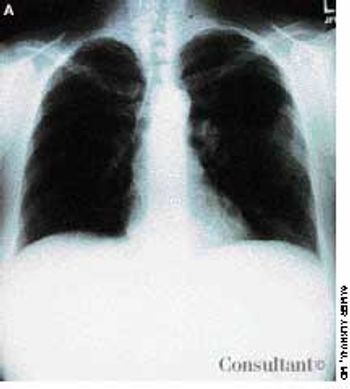

Ten days before presenting for evaluation, a 69-year-old man began to experience neuralgic pain and noticed the eruption of painful erythematous macules and papules on the right side of his chest. Within 24 to 72 hours, vesicles and pustules arose at the site. One week after onset, several of the lesions dried and crusted.